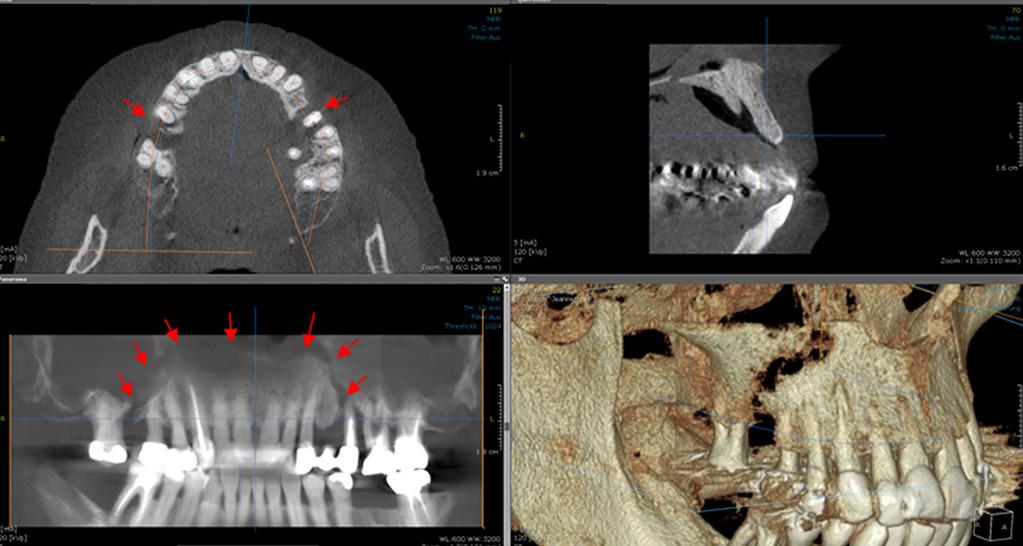

Figures 4 et 5: (stade 3) Patiente présentant une ostéonécrose avancée du maxillaire supérieur ayant entraîné une fracture pathologique spontanée du maxillaire (résultat clinique avec clichés radiologiques correspondants (DVT).

(Photo avec l'aimable autorisation du Dr. H. Thuau)

Abbildungen 4 und 5:

(Stadium 3) Patientin mit fortgeschrittener Osteonekrose des Oberkiefers, die zur spontanen pathologischen Fraktur der Maxilla führte

(klinischer Befund mit korrespondierenden radiologischen Aufnahmen (DVT)

(Bild mit freundlicher Genehmigung

Dr. H. Thuau)